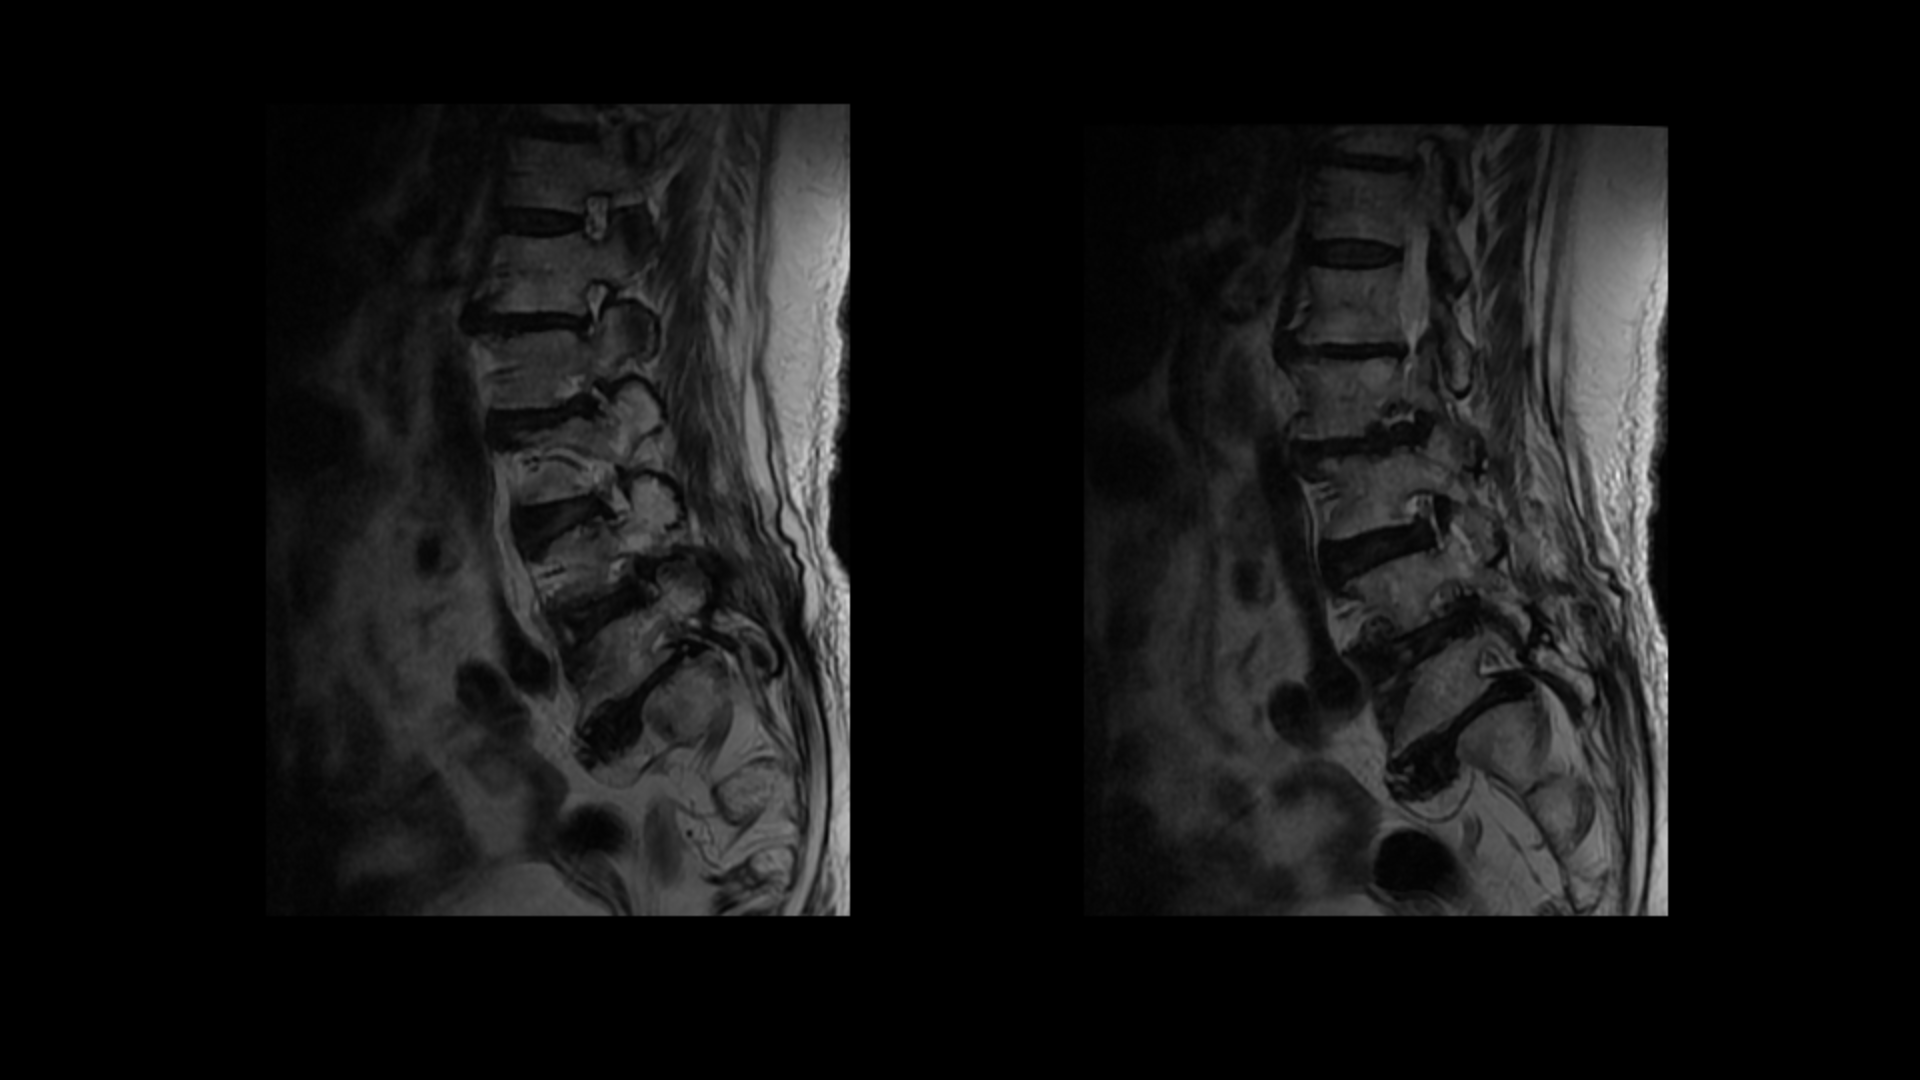

그런데 이분은 허리도 굽으셨는데 척추근육, 특히 허리를 세워주는 기립근을 mri에서 보면 허리 다섯 마디 전체에서 기립근의 근육이 지방으로 변해서 하얗게 보이는 지방화가 심합니다.

이렇게 근육이 지방으로 심하게 변하고 기능이 떨어지면 허리를 펴기가 어렵고 허리가 아플 수 밖에 없습니다. 여기 건강한 기립근과 비교해서 보면 그 차이를 금방 알 수가 있습니다. 기립근 크기도 차이가 크고 하얗게 지방으로 변해버린 부분을 잘 보실 수 있습니다.